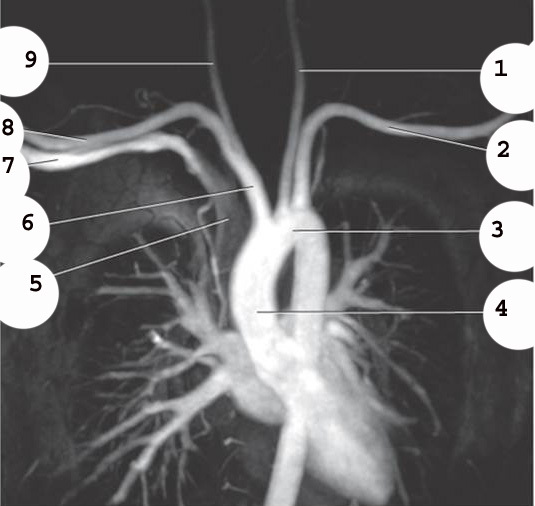

1

Left brachiocephalic vein

2

Braciocephalic Artery

3

sternum

4

L Common carotid A

5

Left subclavian Artery

6

Esophogus

7

Trachea

8

RT brachiocephalic vein (page 325)